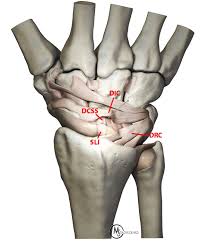

The repair process of ligament tear is different from other soft tissues. The ligaments are stretched, but not torn. A torn ligament causes the wrist bones to move out of their position, which in turn leads to wrist instability as the sprained (torn) ligament can no longer support the wrist bones. As a result, the joint may show abnormal looseness. The ligaments are partially torn. Ligament injuries are graded from one to three based upon their severity. This indicates that the ligament has a. Ligaments are susceptible to injury which is called a sprain. The scapholunate ligament is a key element in stabilizing the foundation of the wrist (the scapholunate joint). Intermediate sprain with partial thickness tear of the ligament A grade 1 (mild) sprain usually involves stretching of a ligament. Types of wrist ligament tears. Is a partial sprain without instability.

The ligaments have fairly low vascularity (blood supply) that is why it takes much more time to heal. This is a severe sprain with a complete tear of the ligament. Intermediate sprain with partial thickness tear of the ligament Wrist ligament tears may be classified as: The scapholunate ligament connects the scaphoid to the lunate. There are two major types of wrist sprains that are based on location. A grade 1 (mild) sprain usually involves stretching of a ligament. Grade 2 sprains can involve a ligament being partly torn, which can affect your range of movement grade 3 sprains are when the ligament is torn, sometimes fracturing the bone as it tears (avulsion fracture). Although there are many ligaments and injuries in the wrist, a scapholunate ligament tear is the most commonly injured. The most important part of the ligament is on the back (dorsal side) of the wrist. Wrist ligaments are stretched and have microscopic tears; A grade 3 (severe) sprain involves a complete rupture of one or more ligaments that may pull off a bone fragment (avulsion fracture). This is a mild sprain that damages the ligament but does not cause significant tearing.